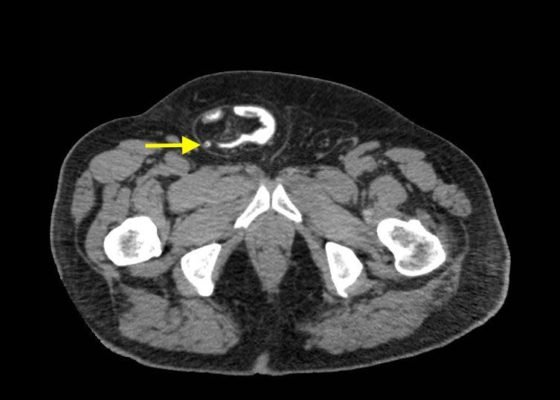

An Elderly Male with Amyand’s Hernia

DOI: https://doi.org/10.21980/J80D13Ultrasound of the right scrotum shows a right inguinal hernia with an air-containing loop of bowel (white arrow) and a non-compressible appendix (yellow arrow). Coronal and axial views of abdomen-pelvis CT show a right inguinal hernia containing a loop of small bowel (white arrow) and appendix (yellow arrow).